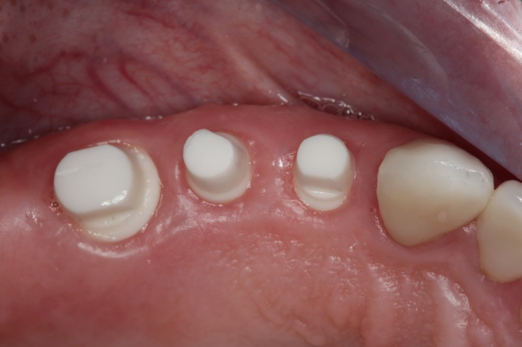

Fig 11. Preoperative healed sites.

Figure 11

Fig 12. Ceramic implants placed and sutured.

Figure 12

Fig 13. Lateral view after placement.

Figure 13

Figure 10 through Figure 13 show the preoperative x-ray and the sequence of beginning with healed sites through the surgical placement of the implants. The implants were protected by an Essix-style wound-protection removable retainer for approximately 12 weeks. After the integration phase, the implants and the natural dentition were prepared using traditional crown-and-bridge high-speed diamond and zirconia cutting burs to remove decay and existing restorative materials, to complete and refine the natural-tooth structures to receive full-crown coverage, and to prepare and refine gingival margins of the zirconia implants where needed.